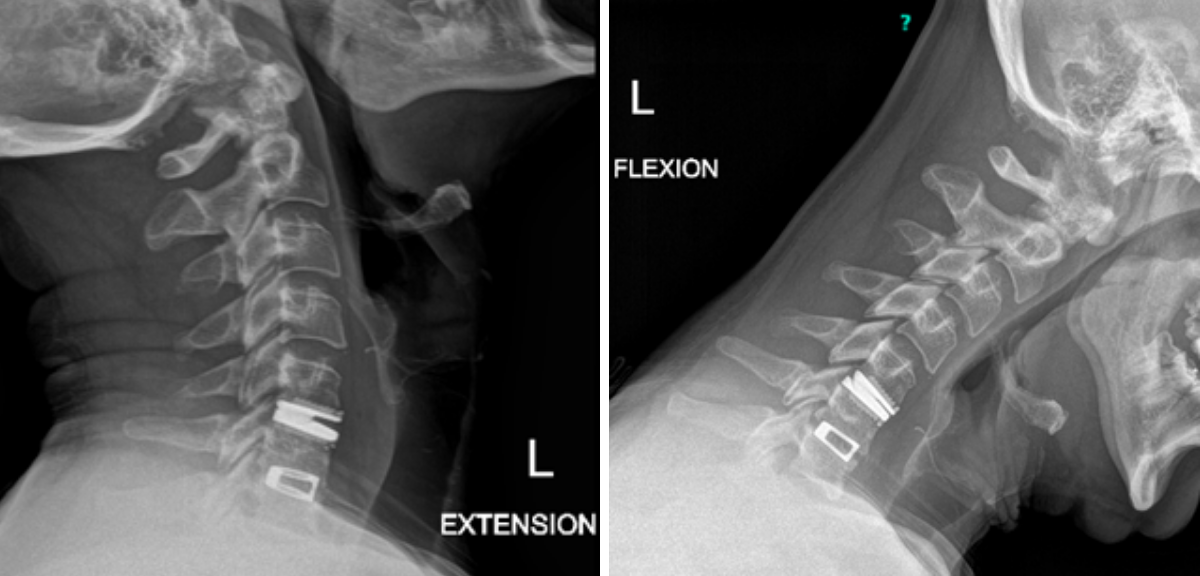

Figure 1.

This 77-year-old man with a history of stroke in 2013 presented to a small community hospital with aphasia upon awakening. Given the unclear timing of onset of his symptoms he was not deemed a candidate for intravenous thrombolytic. His NIHSS was 2 in the emergency room. He was admitted to the hospital where a CT (Figure 1) and CTA were performed showing a left frontal small infarct and severe extracranial carotid stenosis on the left. MRI could not be performed because of the patient’s pacemaker. Examination was significant for an awake gentleman with normal cranial nerve function and normal motor exam but significant expressive aphasia. Receptive aphasia was intact. He was placed on Aspirin.